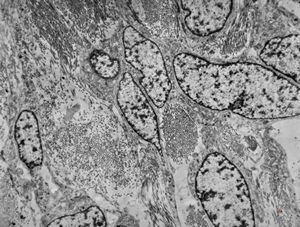

M,50y. | Pneumocystis carinii - lung